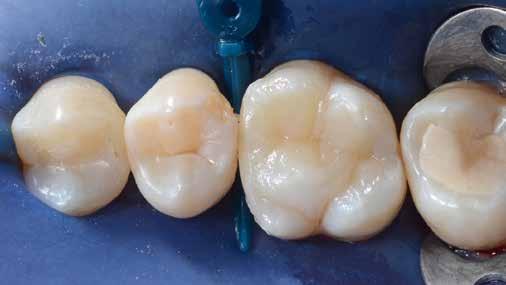

A korábban rutinszerűen használt amalgámtömések mára a legtöbb páciens számára esztétikailag nem elfogadhatóak, hanem fogszínű, természethű restaurációt várnak el. Kaméleon effektussal bíró kompozitokat használva, akár szakavatott szem számára is láthatatlan módon, funkcionálisan és esztétikailag is helyreállítható a fog. Az adhezív technika fejlődésének és az alacsony zsugorodási stresszel bíró kompozitoknak köszönhetően a kiterjedtebb II. osztályú üregek direkt módon is felépíthetőek. Megfelelő protokollokat követve lépésről lépésre kiszámíthatóan elérhető a kívánt végeredmény.

Az 53 éves hölgy páciens jobb felső 6-os fogában látható amalgámtömés cseréje volt a cél. A tömés mellett secunder caries és az amalgám következtében létrejött mesialis zárólécen áthaladó repedés, továbbá mesialis caries figyelhető meg (1. ábra). El kellett kerülni, hogy a tömés kifúrásakor az amalgámtörmelék a páciens szájába kerüljön, esetleg ebből valamennyit lenyeljen, a kezelés első lépésként kofferdám izoláció került fel a jobb felső kvadránsba (2. ábra). A kapocs a 1.7 fogra került, ezzel kényelmesen helyet teremtett a későbbiekben felkerülő matricarendszernek. Az egyszerre több fog izolálása lehetővé teszi, hogy a szomszédos fogak referenciául szolgáljanak a restauráció felépítése közben.

A régi amalgámtömés eltávolítását követően caries indikátor segítette a carieses laesio megfelelő kitisztítását a pulpa expozíciója nélkül. Ezután kerülhetett sor az ideális üregdesign kialakítására, továbbá a zománcszélek finírozására (3. ábra) Az approximális box megnyitása során az alátámasztatlan zománcprizmák eltávolításra kerültek, ezzel is csökkentve a secunder caries képződés veszélyét. Az így kialakuló forma elősegíti a matrica megfelelő adaptációját, végül pedig az approximális box határainak a hozzáférhetőségét, így finírozás során ez jobban kontrollálható és polírozható.

A Palodent V3 matricarendszer felhelyezését követően a zománc 10 másodperces szelektív savazása, majd lemosása és leszárítása után történt a kavítás bondozása Prime & Bond Universallal.

Kulcslépés: a II. osztályú üreget a matricarendszer segítségével I. osztályúvá lehetett átalakítani.

A pontosabb széli záródás érdekében célszerű a matrica illesztési határába némi folyékony kompozitot felvinni (NeoSpectra ST flow A2), majd megvilágítás nélkül a zárólécet paszta kompozittal (NeoSpectra STHV A2) felépíteni, miközben a kifolyó fölösleges folyékony kompozit eltávolításra kerülhet. Így ki lehetett használni és kombinálni a két különböző konzisztencia előnyeit.

A polimerizációt követően kerülhet sor a matricafeszítő gyűrű, valamint a matrica eltávolítására. A Palodent V3 fülekkel ellátott matrica kialakításának és a speciális PinTweezers csipesznek hála, a feszes kontaktpont ellenére a matrica könnyedén eltávolítható. Az éket viszont a kezelés végéig

célszerű bennhagyni, elkerülve egy esetleges nemkívánatos vérzést (4. ábra)

A matrica és gyűrű nélkül az approximális fal magassága, valamint a szomszédos fogakhoz viszonyítható dimenziók jobban megállapíthatóak. A jobb térlátás és a nagyobb mozgástér precízebb eredményhez vezet, csökkentve ezzel az utólagos finírozás mértékét, továbbá a részletgazdagon kialakított anatómiai struktúrák torzulásának az esélyét. Az üreg mélyebb részei SDR Plus A3-mal kerültek feltöltésre, majd NeoSpectra STLV A3-mal kiegészítve vált teljessé a dentin pótlása (5. ábra), ezzel létre lehetett hozni egy homorú formájú kromatikusabb alapot.

Ezt követően csücsökről csücsökre haladva a felső hatosokra jellemző anatómiai struktúrák, megfelelő orientációval bíró csücsöklejtők és elsődleges barázdák Neo Spectra

HV A2 anyagból kerültek kialakításra (6. ábra). Apró „kompozit-hurkákkal” kiegészítve létrehozható a csücskökön belüli tagoltság, ezzel kialakítva a másodlagos barázdarendszert és egy sokkal kidolgozottabb anatómiai struktúrát (7. ábra). A fogorvos esetleges „művészi hajlamát” is figyelembe véve, a természethű megjelenés barázdafestéssel (Micerium - Stain Brown 2) még tökéletesebb lehet (8. ábra). Ezzel a korábban részletgazdagon kialakított ba-

rázdarendszer kiemelhető, és optikailag fokozható a gödröcskék mélysége is.

A restauráció megfelelő polimerizációja után célszerű a kofferdám nyújtotta retrakciót kihasználni, és a restauráció széli záródásában levő esetleges kompozitfölösleg elfinírozását jobb rálátás mellett elvégezni (9. ábra). Ebben nagy segítségünkre lehet az Enhance rendszer, mely a kompozitot nagyon szépen elsimítja, de a természetes fogszövetet nem bántja.

A matricázott terület széli záródásának a kidolgozásában az EVA polírozó (10. ábra) lehet a segítségünkre, amellyel a gingiva sérülése megelőzhető, és a kialakított feszes kontaktpont sem kerül redukcióra (11-12. ábra)

A kofferdam eltávolítását követően kerülhetett sor az occlusio beállítására csücsöklejtők domborúságának a redukciója révén (13. ábra). A harapás gyémántfúrókkal történő beállítása után a polírozás Enhance rendszerrel történt, melynek végső lépéseként a PrismaGloss használatával (14. ábra) nyerhette el a restauráció a végső fényességét (15. ábra)

A ma rendelkezésre álló modern eszközöknek és anyagoknak hála II. osztályú üregek direkt módon kiszámíthatóan restaurálhatóak. A matricarendszernek köszönhetően helyreállítható a feszes kontaktpont, a „kaméleon effektussal” bíró kompozit pedig a tömés integrációjáért felel. A megfelelő adhézió, a precízen kidolgozott széli záródás és a plakkréteg megtapadását nehezítő polírozott felszín a kezelés hosszú távú sikerének a garanciája. Mindezek együtt egy hosszú távon tartós, funkcionális és esztétikai rehabilitálást tesznek lehetővé.